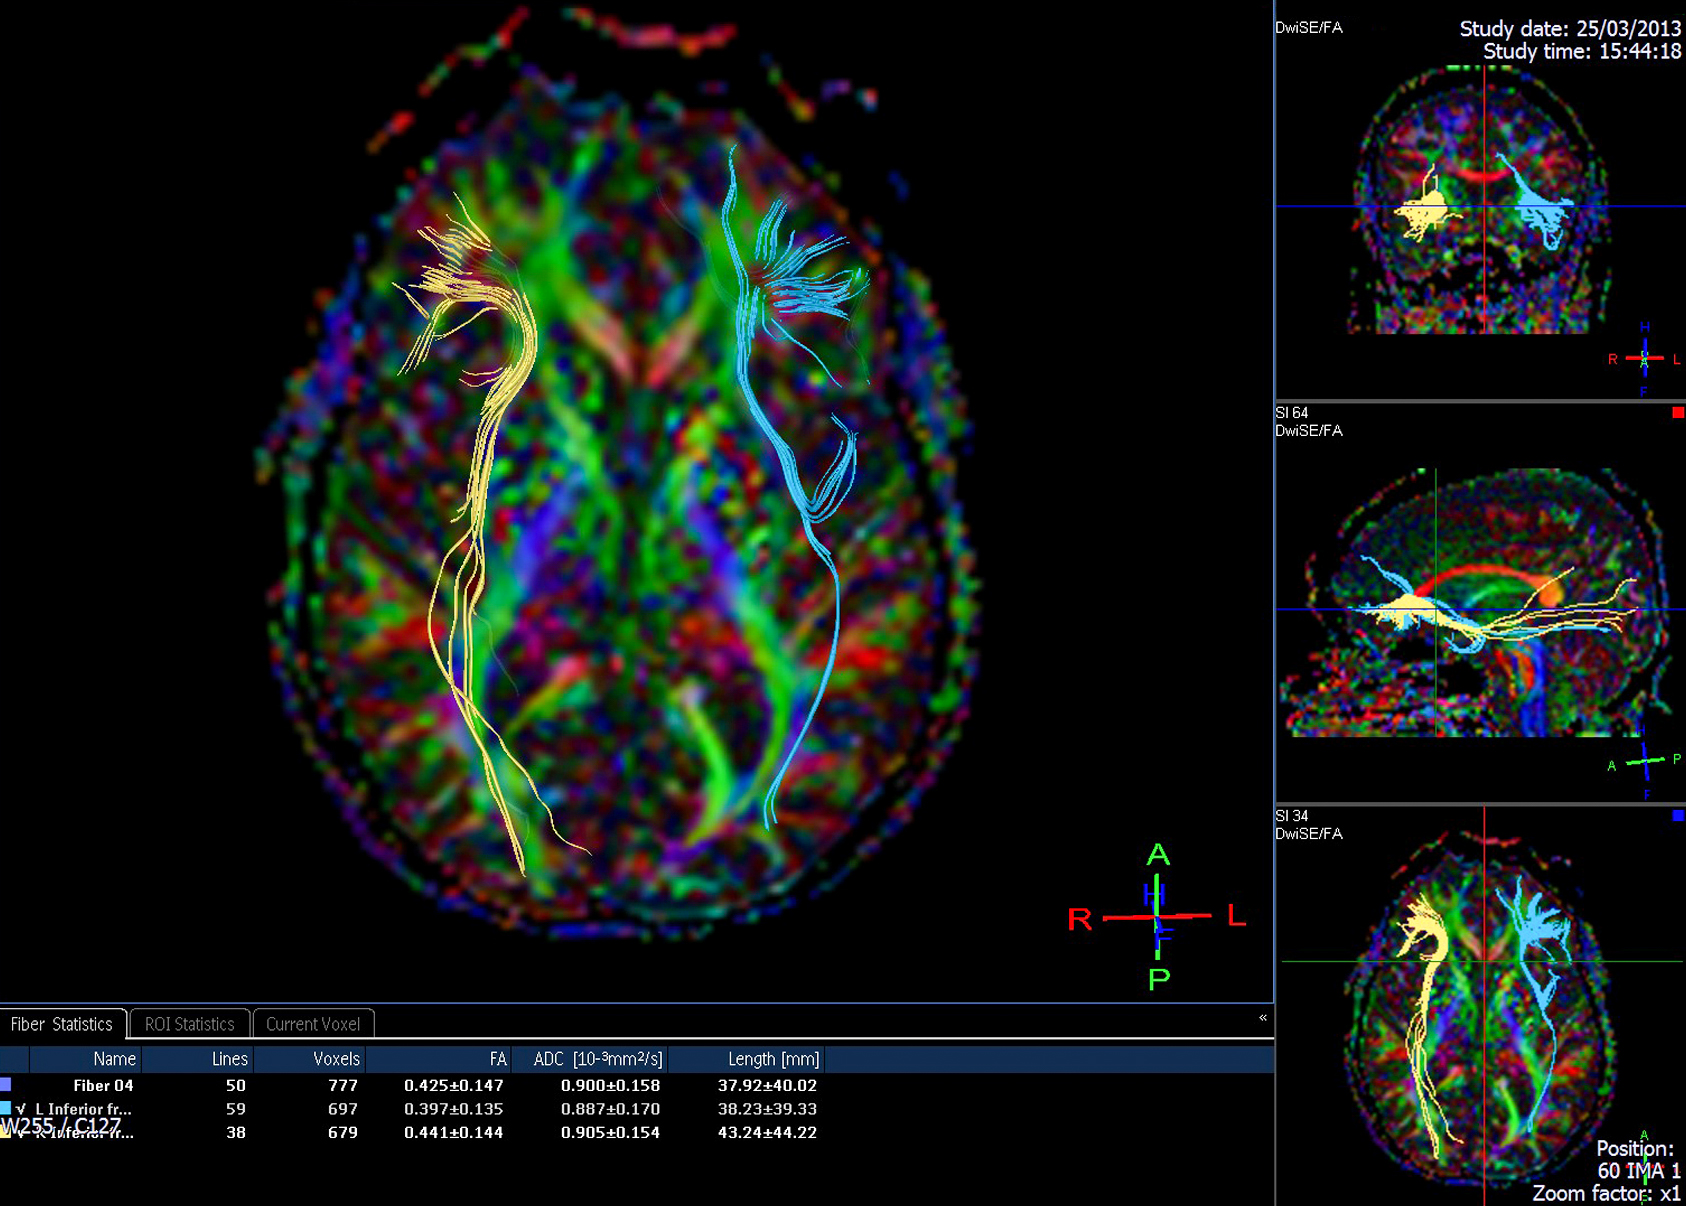

Diffusion tensor imaging (DTI) tractograpy. The color-coding of

Diffusion Tensor Imaging (DTI) - Fiber Tracking - Imagilys

Diffusion Tensor Imaging (DTI) - Fiber Tracking - Imagilys

Diffusion Tensor Imaging (DTI) - Fiber Tracking - Imagilys

A) Diffusion tensor imaging (DTI)-based whole-brain tractogram in